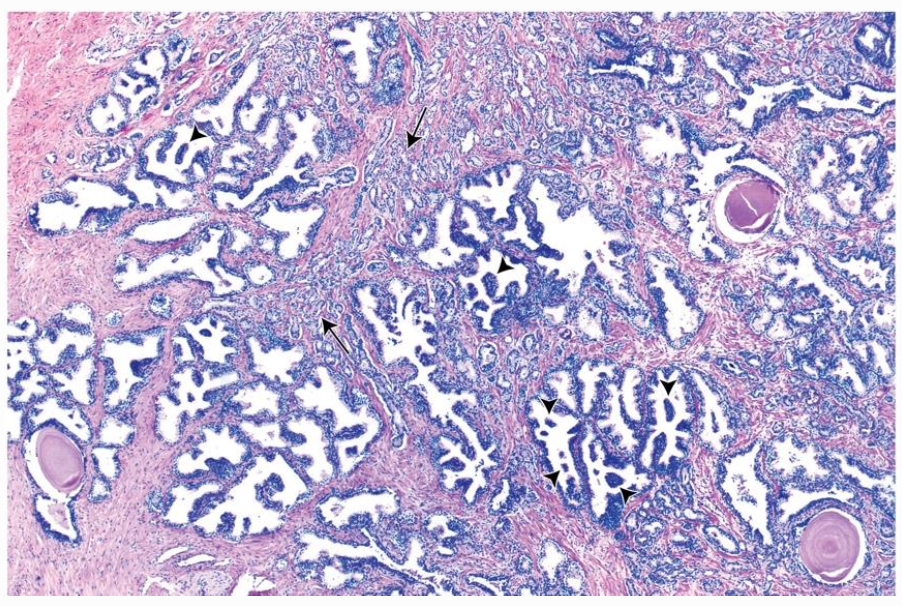

- Tubuloalveolära seromukösa körtlar omgivna av fibromuskulärt stroma (glatt muskulatur + kollagena fibrer). Trichromfärgning visar stroma blått.

- Corpora amylacea (lamellerade konkrement) ses ofta i lumen hos vuxna och ökar med ålder eller stagnerat sekret.